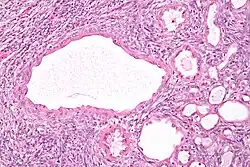

Micrograph of a cystic nephroma (left of image). Normal kidney is seen on the right. H&E stain.

A cystic nephroma, also known as multilocular cystic nephroma, mixed epithelial stromal tumour (MEST) and renal epithelial stromal tumour (REST),[1] is a type of rare benign kidney tumour.